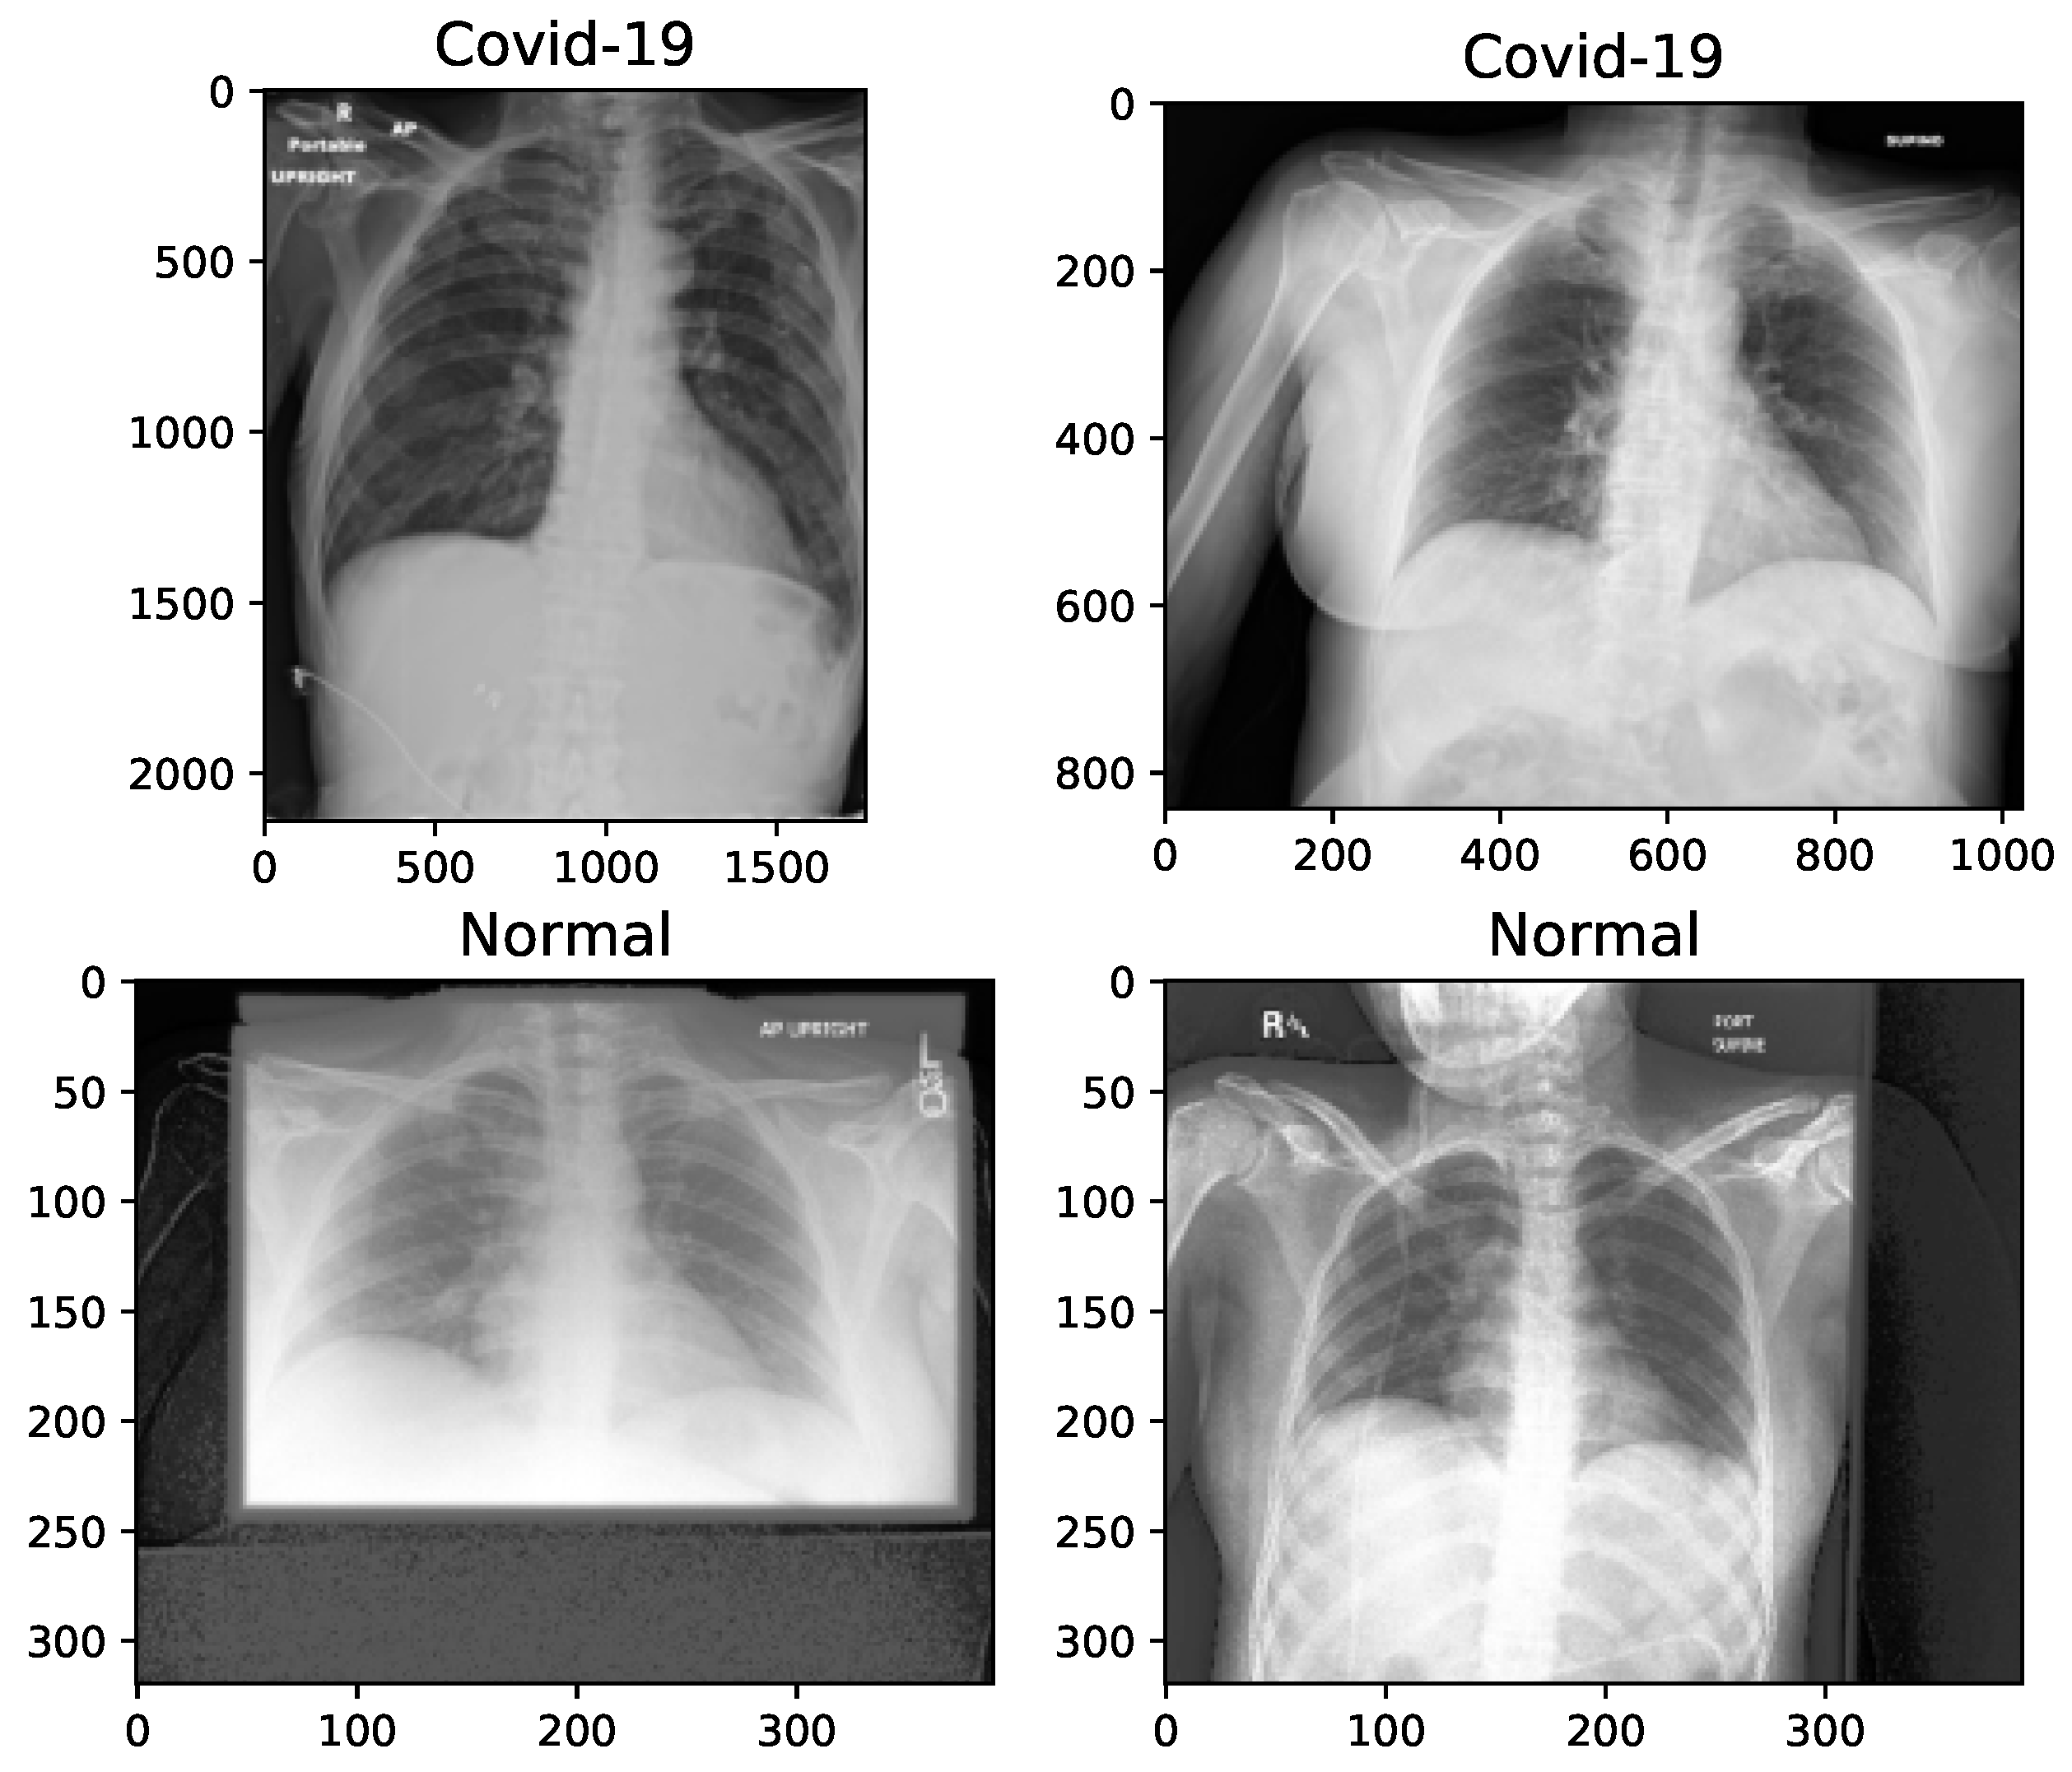

The data used in this work has been collected from “The Cancer Imaging Archive (TCIA)” [58]—a collection of X-rays and CT images—related to patients with positive COVID-19 tests [59]. We have separated 253 X-rays from the CTs (last modification in September 15, 2020). The related information has been collected from 105 patients, both females and males, with a minimum age of 19 and maximum age of 91 years old. The mortality was of 10 out of 105 patients. The images, provided in the dataset, have been of very low resolutions, and in addition, each image has been presented in a different resolution to other ones. The original images have been in Digital Imaging and Communications in Medicine (DICOM) format. Normal X-rays are selected randomly from the data collection of Mendeley [60] in the ‘jpeg’ format. Age, sex and any other information regarding the patients of this dataset is not provided due to privacy concerns. The difference of image sizes and the need to manipulate them for some random samples are shown in Figure 1.

The key problem with small and unbalanced datasets is that models trained with them may not be generalized. Hence, these models suffer the issue of overfitting. Data augmentation is an approach to reducing overfitting, by which we are able to increase the amount of data, with only using available data [61]. In this paper, 100 images, with an equal proportion of classes, is held out for testing the model, and the number of samples of each class is balanced by increasing the number of COVID-19 chest X-rays to 500 images. The augmented images are randomly selected from the original X-rays. In total, 1000 (500 normal + 500 COVID-19) images are employed for the training phase. On the other hand, image preprocessing is needed, because the images are not of the same size, as shown in Figure 1, and therefore are converted into the same size for training. In Table 1, we present the manipulations that are applied to the X-rays, before proceeding with the augmentation.

Figure 1. X-ray image samples of two categories before image manipulation.